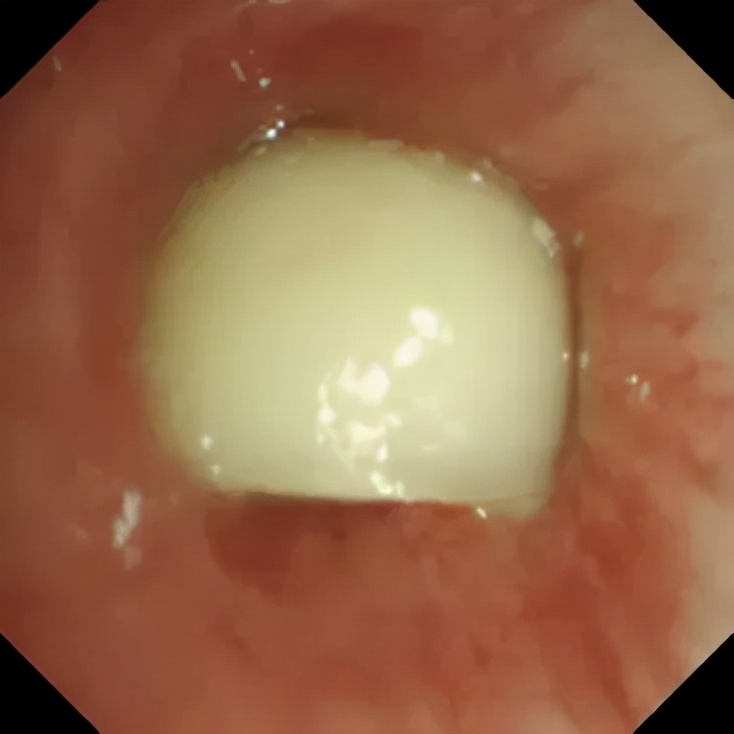

图1:支气管异物

图1,一位64岁的老年女性,晚上进食时,边吃花生米边跟家人大声说话,一不小心就把花生米呛到气道了。患者当时就出现剧烈咳嗽、憋气的症状,开始患者想通过咳嗽把呛入气道的花生米给咳出来,但是花生米不但没有咳出,反而越陷越深,最后落到了右侧支气管里。这位患者以为第二天异物有可能会咳出,因此当晚没有到医院就诊,结果第二天早上咳嗽、憋气的症状还是存在,异物也没有咳出,遂来到北京清华长庚医院呼吸与危重症医学科就诊。医生立即为其安排了全麻下支气管镜检查,最终成功取出了异物,为半颗剥了皮的花生米。

图:支气管镜下取出的半颗花生米